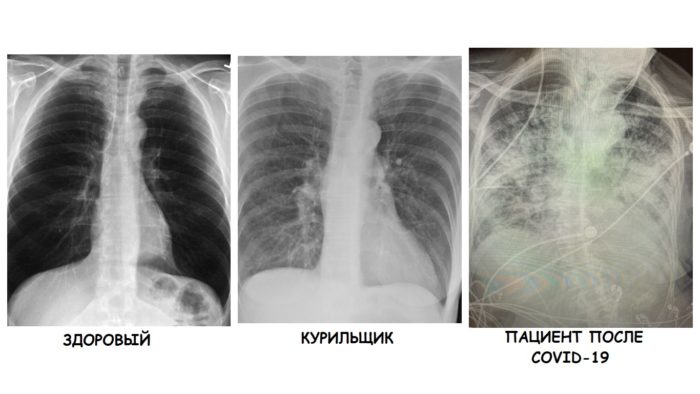

Врач сравнила рентген-снимки здорового, курильщика и больного коронавирусной инфекцией